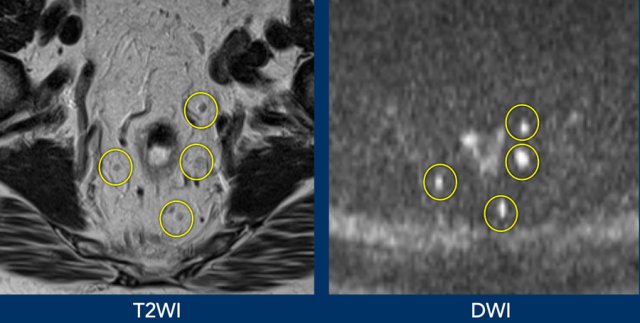

Lymph nodes like other lymphoid tissues including the spleen have a dense cellular structure resulting in restricted diffusion and a high signal on DWI.

As a result, DWI can be helpful in detecting lymph nodes but is less suitable for lymph node characterization as both benign and metastatic lymph nodes will show high signal.

Images

Better visualisation of lymph nodes on DWI compared to corresponding T2WI.